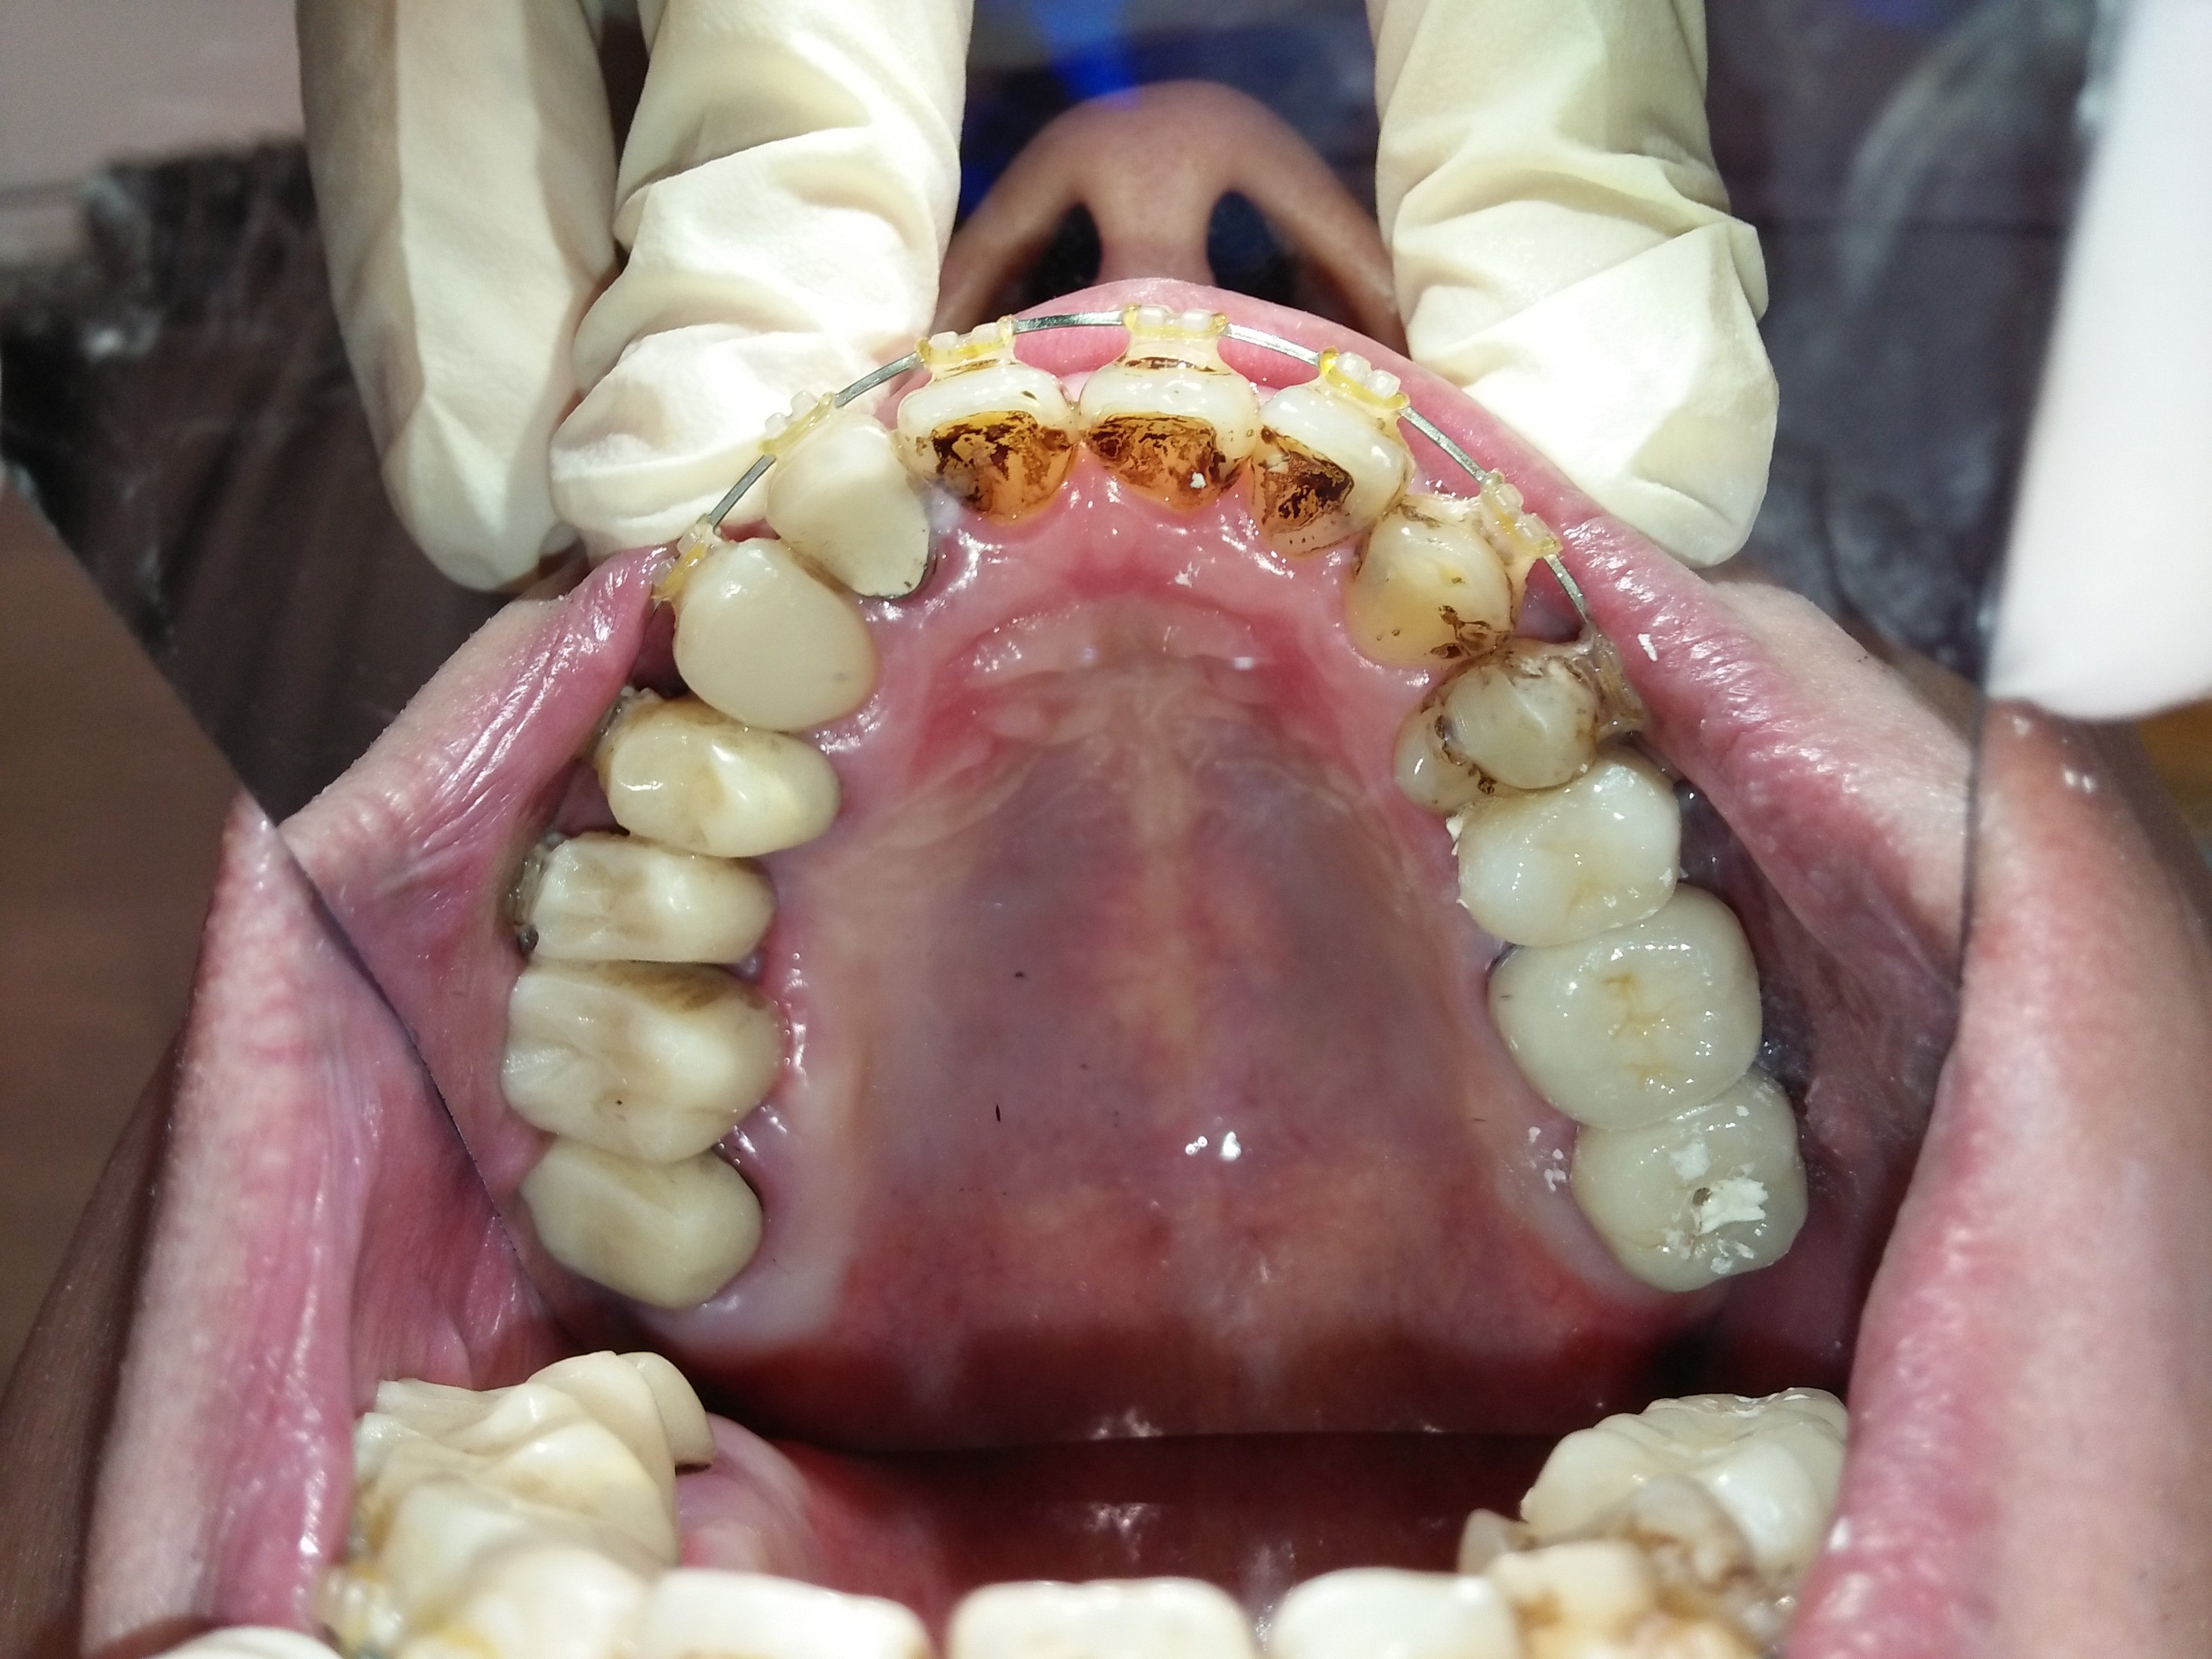

患者於原診所處理牙齒,僅是補牙、抽神經、做假牙的無限輪迴,牙齒壞了做牙橋,牙橋壞了補骨準備植牙,但因患者有疑慮,牙齒始終做不好,上顎假牙總是脫落、總是在看牙醫;決心換家評估。在聽過醫師仔細的分析後,決心要改變自己之前的觀念,接受醫師全口重建的治療方式。

這才發現原來補骨醫師技術有別,不是有補就好,蛀牙也不是一再重複處理讓牙齒神經反覆受刺激;需要先處理咬合、排列的問題,再將缺牙、蛀牙和前牙美觀合併處理,不但解決了牙縫塞東西造成蛀牙不斷,也讓牙齒排列改變改變外觀。

改變排列及牙齒上下相對位置,才能讓咬合和受力分配較佳並穩定,不會產生牙縫遭受直接衝擊的問題。